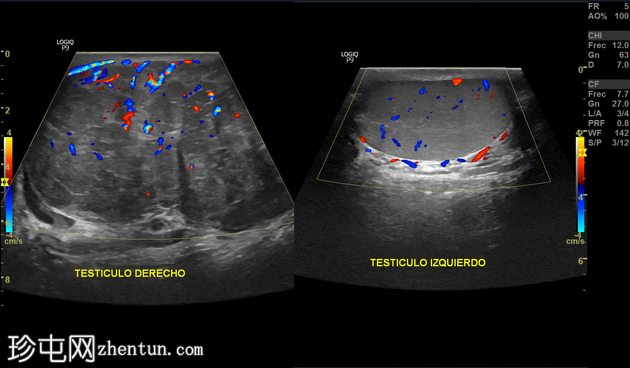

右侧睾丸:

明显肿大(97 × 63 × 81 mm;估计体积:262 cc)。正常回声纹理完全被一个异质性、以低回声为主的肿块所取代,肿块内可见线状回声。彩色多普勒显示血流信号增多。肿块局限于鞘膜内,未见侵犯邻近结构。由于肿块压迫,附睾无法显示。蔓状静脉丛血流信号正常,Valsalva动作反应正常。

左侧睾丸:

大小、形状和回声均正常。睾丸纵隔完整。附睾长约10毫米,回声均匀。彩色多普勒血流显像和Valsalva动作反应均在正常范围内。

印象:

右侧睾丸内可见实性、不均匀、以低回声为主的肿块,怀疑恶性肿瘤。需考虑精原细胞瘤或其他肿瘤性病变。

左侧睾丸未见异常。